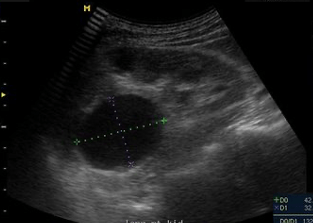

Name this pathology that presents as a spherical structure that does not communicate with the renal collecting system.

What is a parapelvic cyst?